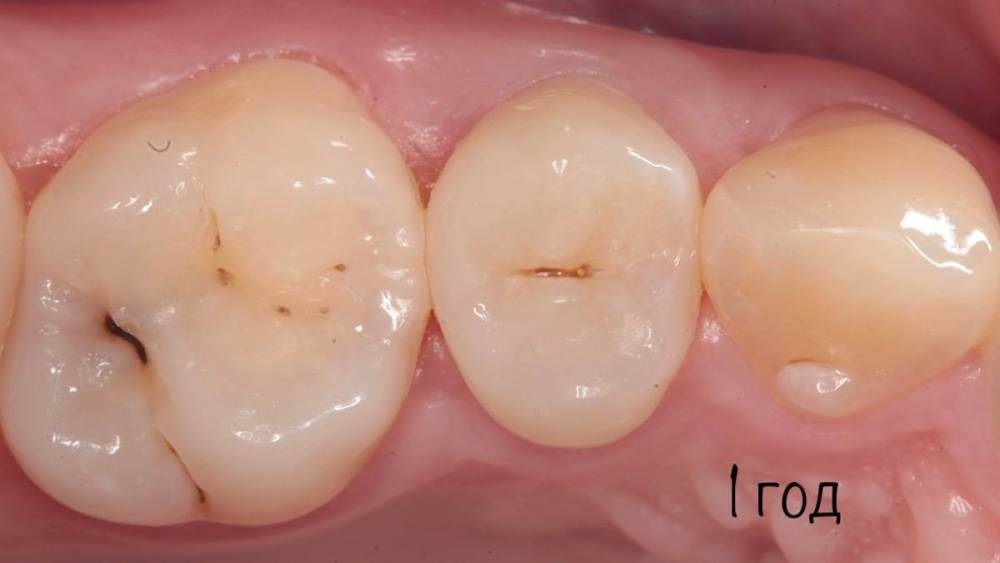

Гарриевич Опубликовано 6 апреля, 2023 Автор Поделиться Опубликовано 6 апреля, 2023 3 1 Ссылка на комментарий

Doc Опубликовано 7 апреля, 2023 Поделиться Опубликовано 7 апреля, 2023 Удивительное рядом. 1 Ссылка на комментарий

Гарриевич Опубликовано 7 апреля, 2023 Автор Поделиться Опубликовано 7 апреля, 2023 5 часов назад, Doc сказал: Удивительное рядом. Хейтеры скажут фотошоп Ссылка на комментарий

Гарриевич Опубликовано 8 апреля, 2023 Автор Поделиться Опубликовано 8 апреля, 2023 6 часов назад, Kolchanov сказал: И сам заработал и неизвестному коллеге-ретритчику помог. А я чего вообще кто то может решить туда лезть?) с виду отличный зуб)) Ссылка на комментарий